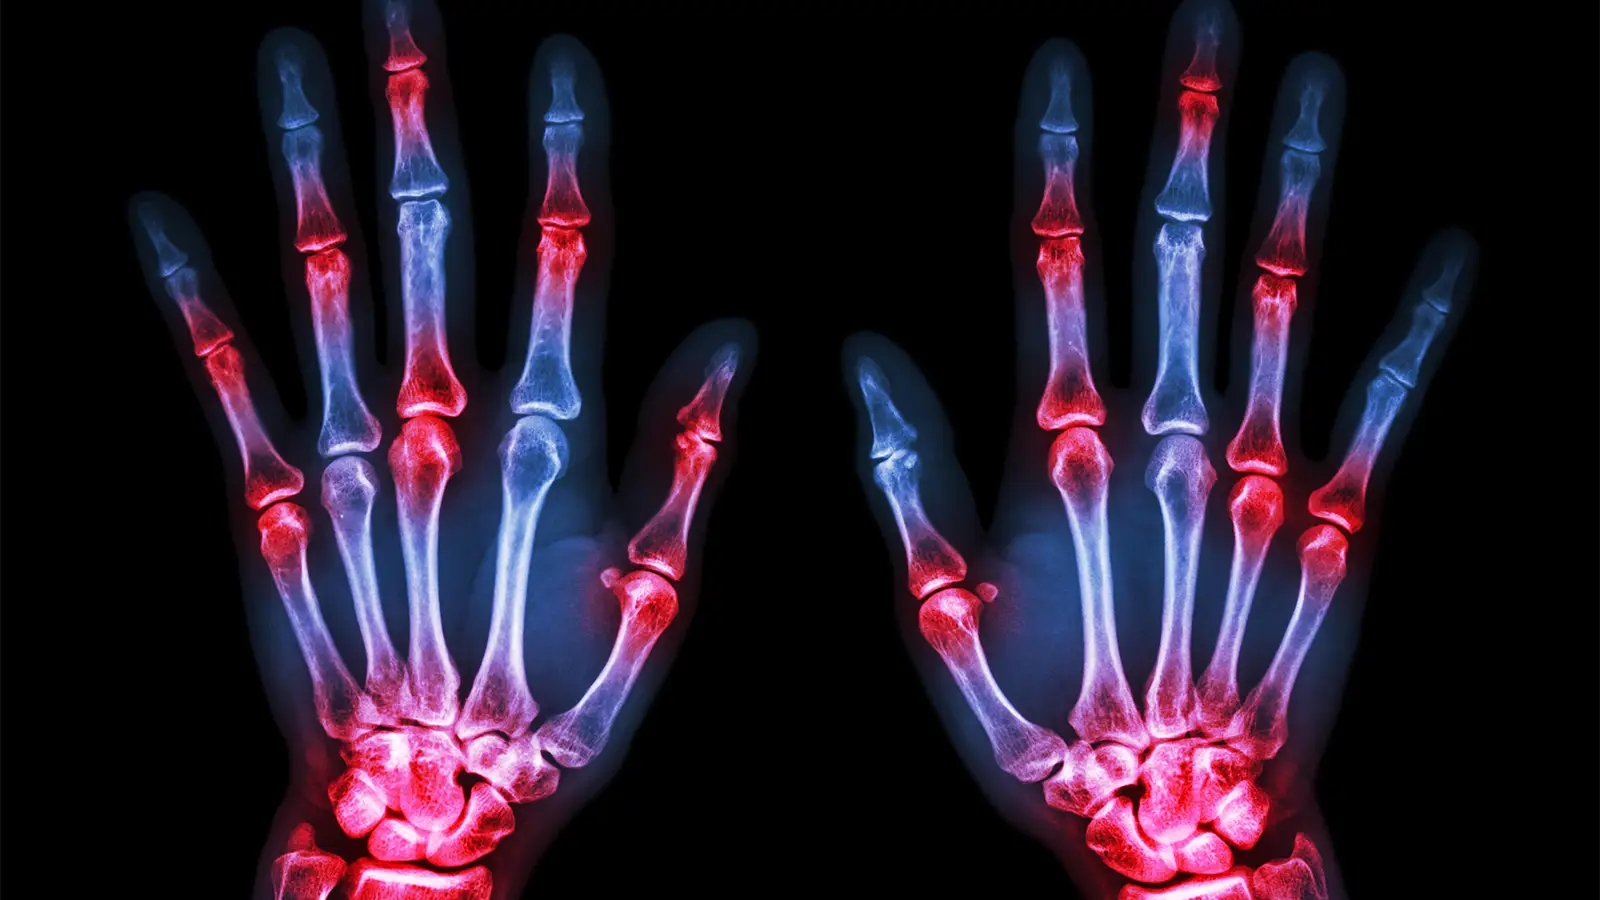

- The Sharp/van der Heijde (SvdH) method for analyzing X-ray images is the standard method for measuring joint space narrowing and bone erosion in rheumatoid arthritis and requires a well-trained reader.

Researchers say a machine learning system for analyzing radiographs of rheumatoid arthritis (RA) patients was able to generate Sharpe/van der Heide (SvdH) scores, a standard method for quantifying joint space narrowing and bone erosion, with higher accuracy compared to human readers.

The system, called autoscoRA, matched human reading scores for joint space narrowing in more than 95% of images of hands and feet, said Thomas Deimel, MD, PhD, of the Medical University of Vienna in Austria, and colleagues.

Performance in scoring erosion was more variable, the group reported. arthritis and rheumatismbut the level of agreement was still considered good. Only 6.3% of hand images and 11.0% of foot X-ray images had a score difference of more than 1 point with the SvdH method.